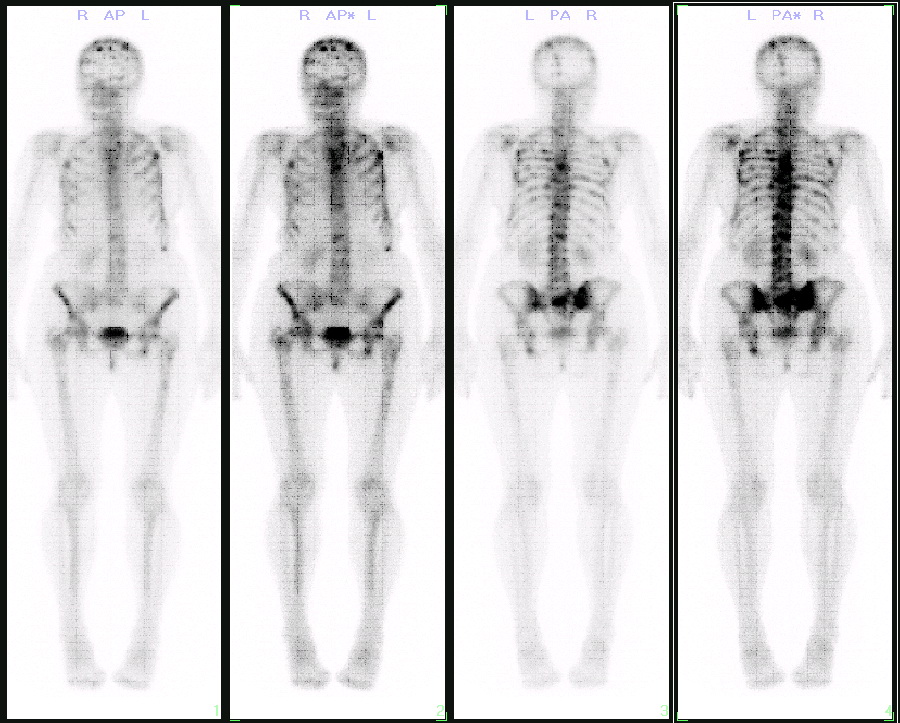

骨扫描正常报告单图片,骨扫描报告单图片

从去年开始,张海燕的右腿会发生持续疼痛,近期到医院进行骨扫描检查.

9g/l; 骨扫描:右侧第1,2,6,7,9肋骨及左侧第1,7,8,9肋骨多发点状放射

骨扫描

骨扫描报告单图片

正常骨扫描图片

正常人全身骨扫描图片

骨扫描显示骨转移图片

全身骨扫描图片

肺癌骨转移骨扫描图片